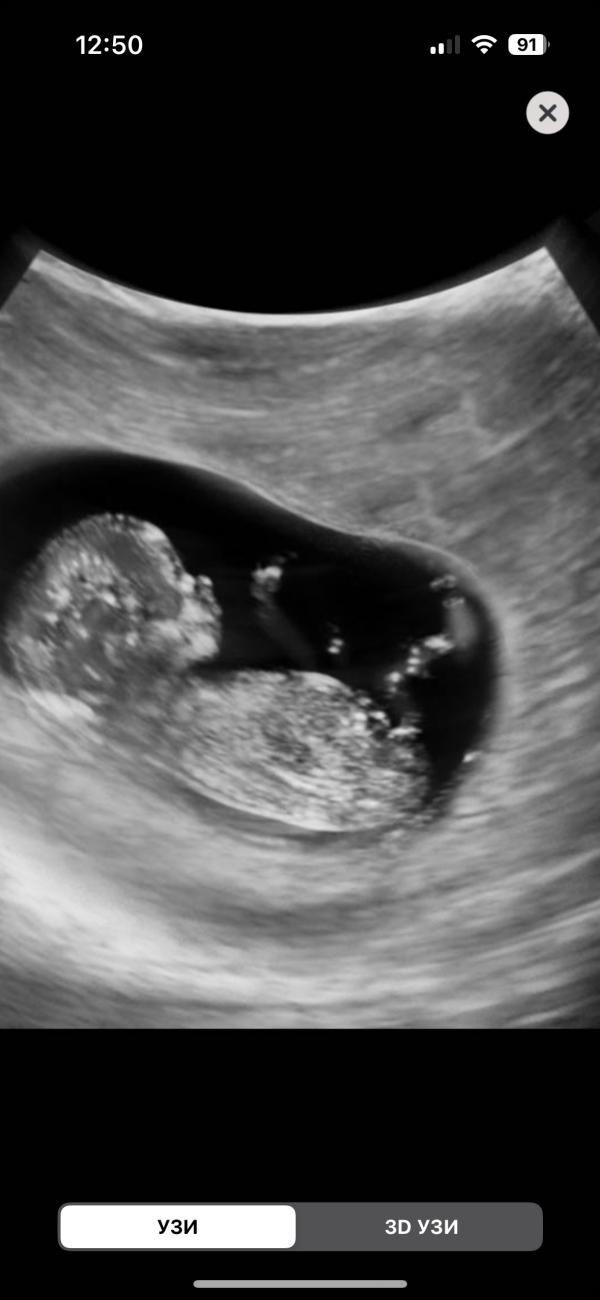

Бейбик уже вот такой🥹🥹🥹🥹🥹😭😭😭😭😭😭

Такой малышочек🥹🥹🥹

Крохотульный🥹уже ручки, ножки есть представляете? 25 числа скрининг первый, так ждуууу🥹🥹🥹🥹

Я не могу это что за персик сладкий🥹